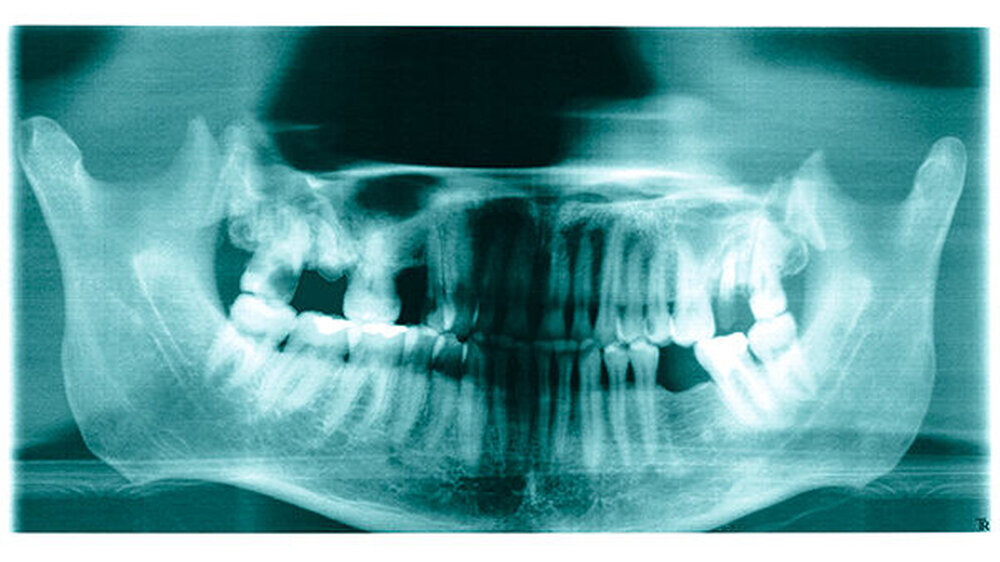

Am 14. März 2003 wurde in der Waal, bei der Gemeine Tiel (Niederlande) ein toter Mann gefunden. Er scheint aus Deutschland zu kommen. Allem Anschein nach lag die Leiche zwischen zwei bis vier Wochen im Wasser.

Das Alter des Toten wird zwischen 30 und 50 Jahren geschätzt. Er hatte schwarze Haare und trug einen Schnurrbart. Seine Größe betrug etwa 175 Zentimeter. Er trug blaue Adidas Sportschuhe in Größe 42, eine blaue Jeans der Marke EDWIN, Größe W31-L32 und dazu einen schwarzen Pullover mit Rollkragen. An seinem rechten kleinen Finger hatte er einen goldenen Trauring. Der Mann war beschnitten.